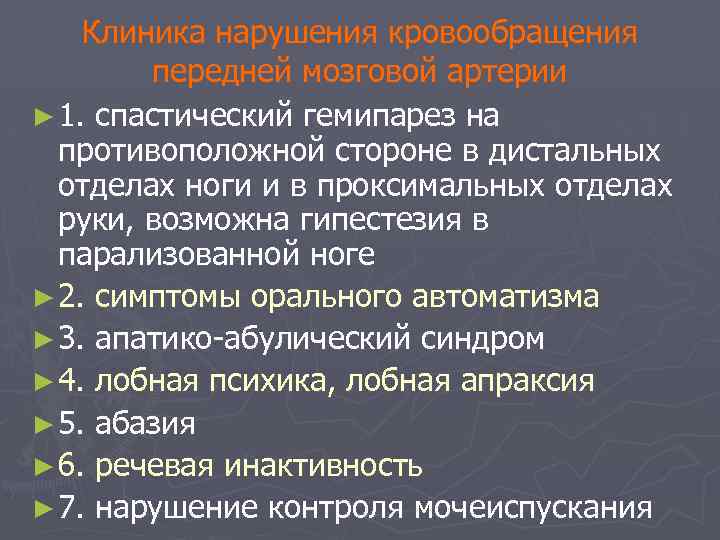

Клиника нарушения кровообращения передней мозговой артерии ► 1. спастический гемипарез на противоположной стороне в дистальных отделах ноги и в проксимальных отделах руки, возможна гипестезия в парализованной ноге ► 2. симптомы орального автоматизма ► 3. апатико-абулический синдром ► 4. лобная психика, лобная апраксия ► 5. абазия ► 6. речевая инактивность ► 7. нарушение контроля мочеиспускания